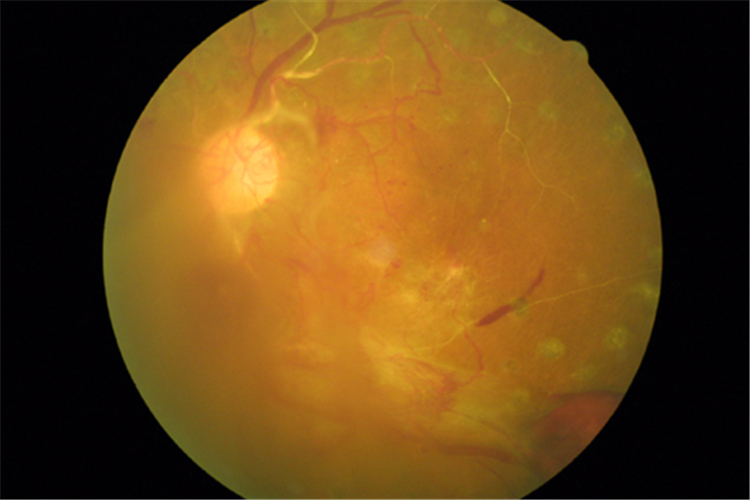

嚴重視網膜脫落

嚴重的視網膜脫落